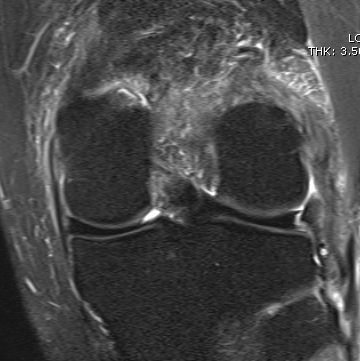

MRI

Chronic proximal avulsion LCL / Popliteus

Sagittal MRI showing torn ACL Coronal MRI demonstrating chronic avulsion LCL fibula head